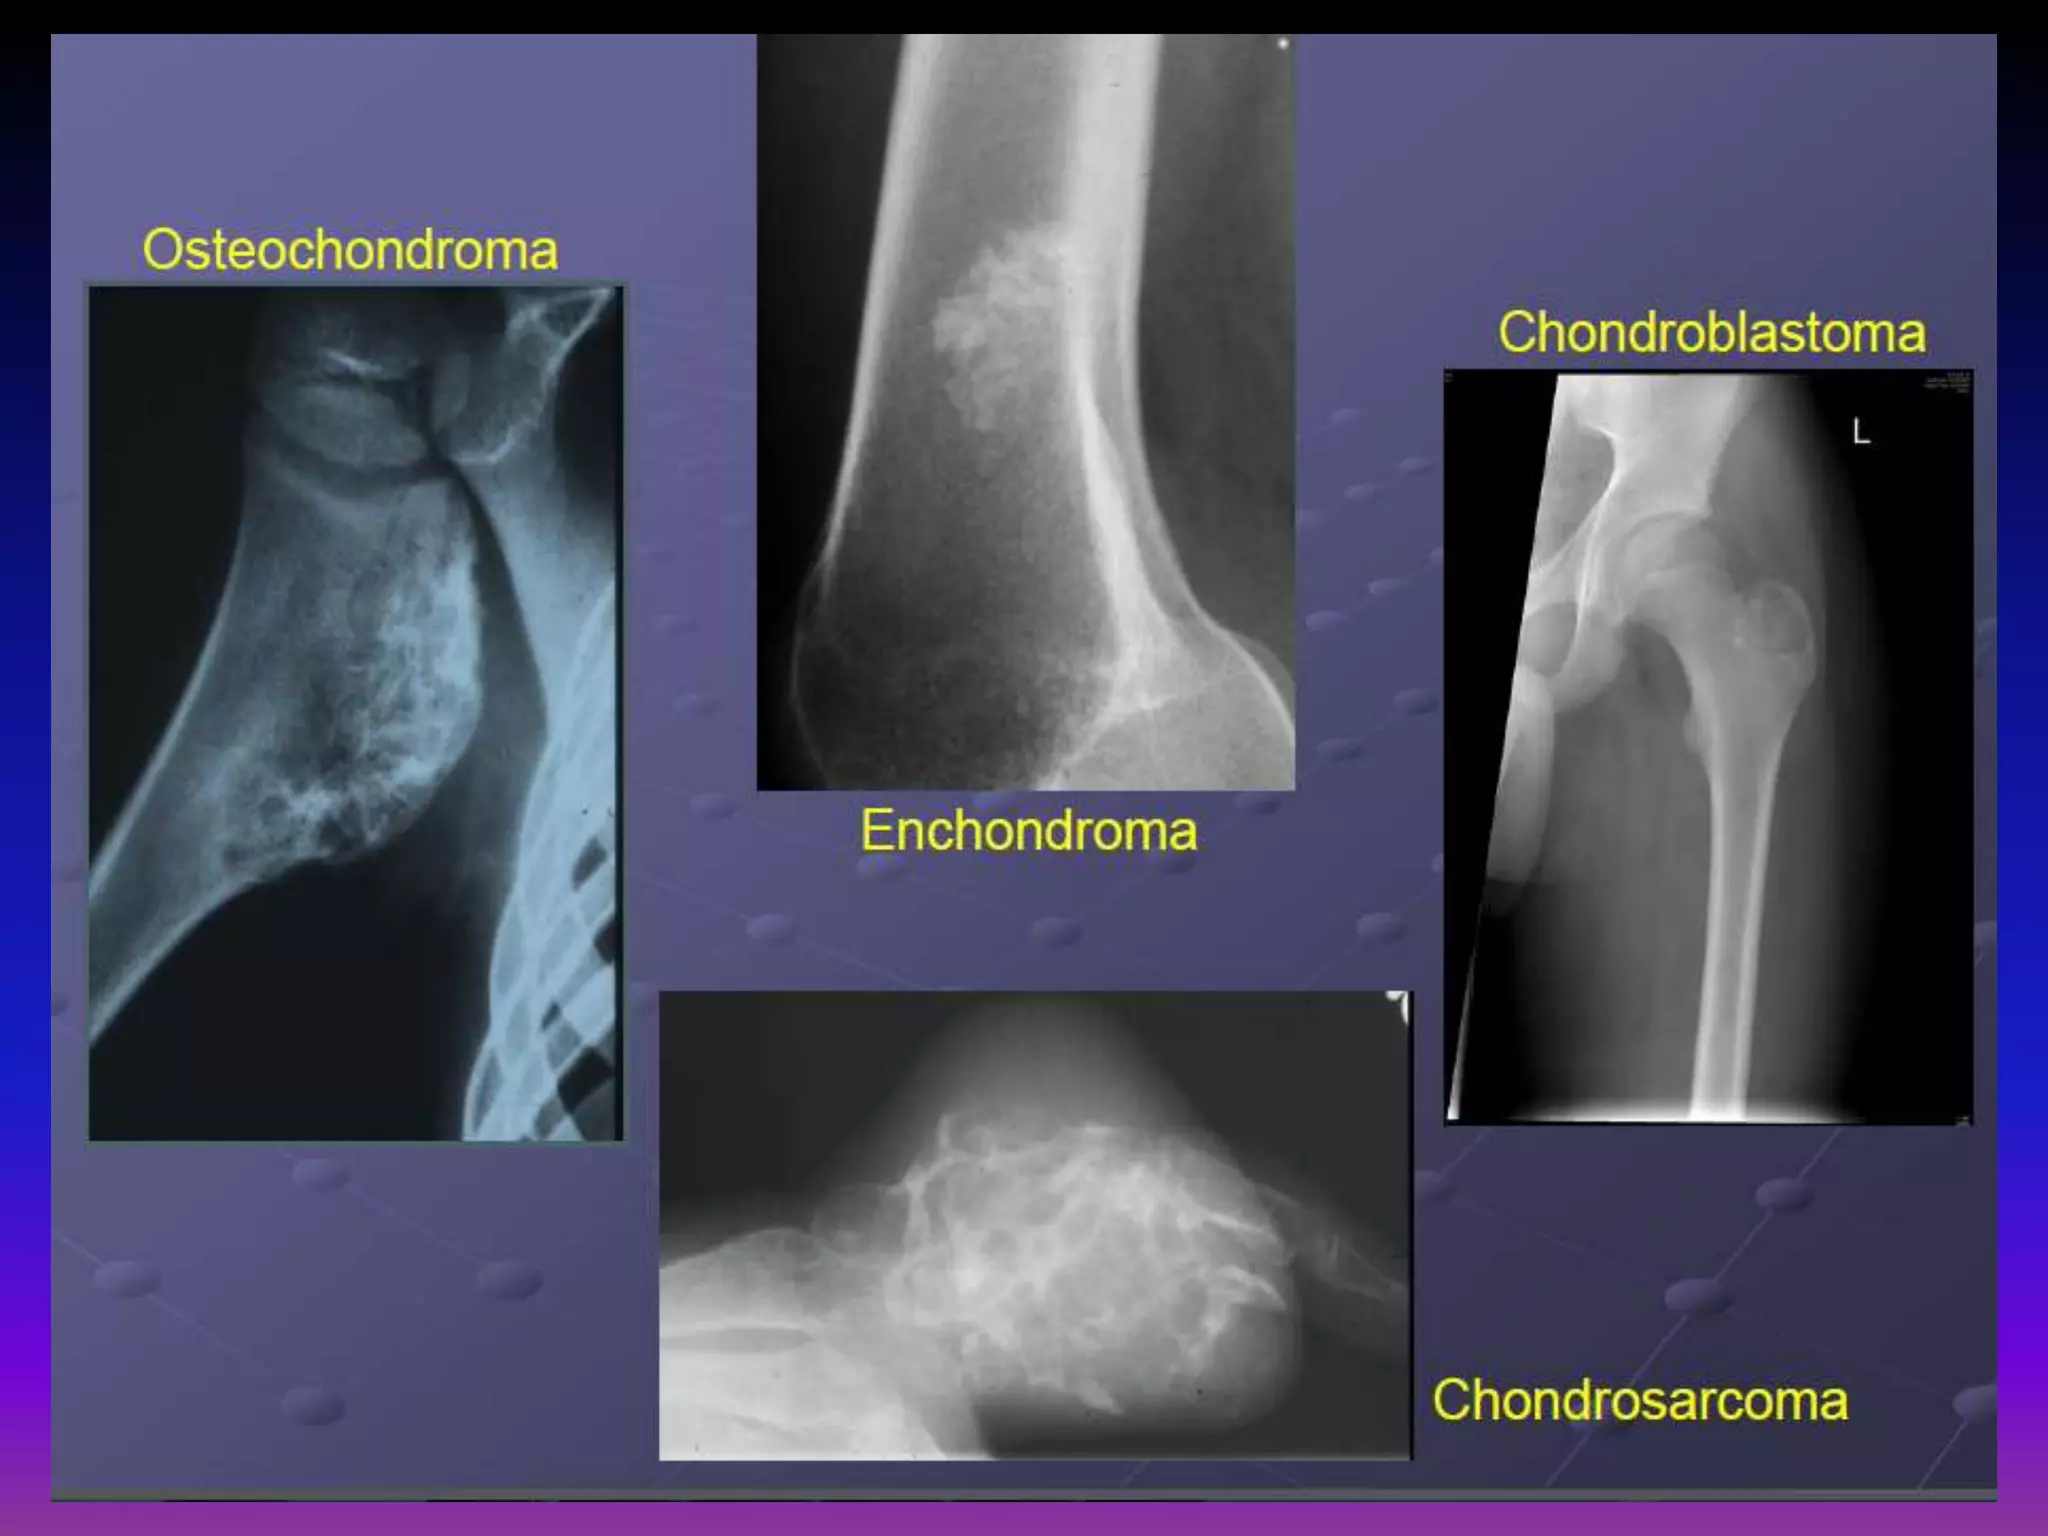

Osteochondroma.

Enchondroma.

Chondroblastoma.

Chondrosarcoma.

Osteochondroma:

Most common benign skeletal tumor

20-50% of all benign bone tumors.

Most frequent in 1 1st and 2nd decade of life

Male : female = 1.5 : 1.

Most often in juxta -epiphyseal / metaphaseal.

area of long bones (distal femur, proximal tibia)

40% around the knee (also shoulder, hip).

Ostechondroma:

Bony exostosis with cartilage cap.

Typically grow away from physis.

Growth ceases after maturity.

Growth after maturity indicates malignant

transformation.

< 1% risk of malignant transformation for solitary lesions.

Solitary, benign,

intramedullary cartilage

forming tumor

Peak incidence in 3 3rd rd

decade

Male : female = 1 : 1

Common in short tubular

bones of hands and feet

Most common primary

tumor in the hand,

usually in the diaphysis.

Rare, benign tumor derived from chondroblasts

(5% of benign bone tumors)

Epiphysis of long bones (also apophyseal

Most common sites

Femur, humerus, tibia

apophyseal) .

Male : female = 3 : 2

Mean age: skeletally immature

May have behavior not normally associated

with benign tumors (pulmonary metastases,

local bone / soft tissue invasion).

Radiographic Appearance:

Lytic well-defined margins

Scalloping or erosion

of cortical bone may be present

Fine calcifications (punctate , rings).

Chondrosarcoma:

Malignant tumor that produces cartilage matrix

Primary chondrosarcoma

Very uncommon, arises centrally in bone, found in

children found children Secondary chondrosarcoma

Secondary Arises from benign cartilage defects

(osteochondroma – surface , enchondroma -

Intra-medullary).

Occurs in 5th or 6th

decade of life.

Male : female = 1.5 : 1

Location: femur,

humerus, ribs, pelvis

Higher risk to occur in

patients with Ollier

disease and Maffucci

Syndrome

(3rd rd or 4th decade of

life).